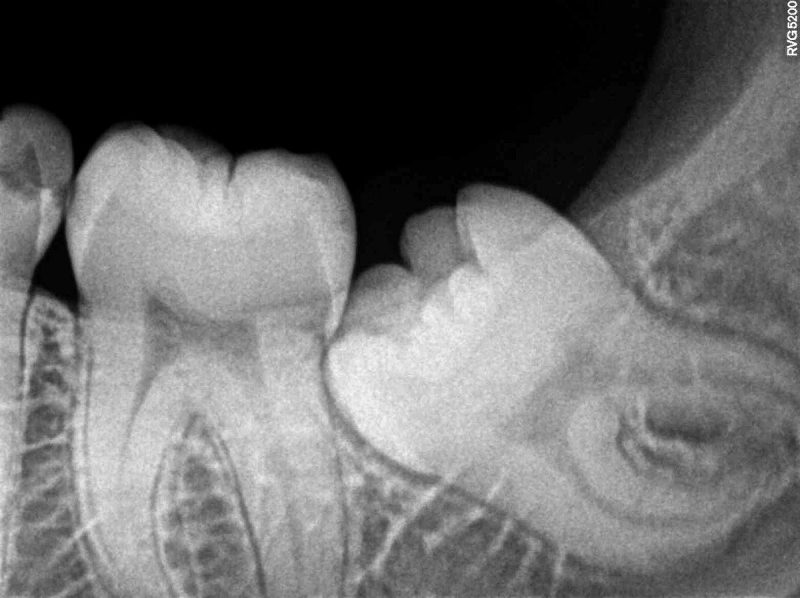

Phim X-quang chẩn đoán răng khôn

Không phải bất cứ trường hợp răng khôn nào cũng cần phải nhổ, và không phải tất cả răng khôn đều phải nhổ. Có thể bảo tồn giữ răng khôn ở những trường hợp sau:

- Răng khôn mọc thẳng, bình thường, không bị kẹt với mô xương và nướu, không gây biến chứng. Trường hợp này nếu giữ lại thì bệnh nhân cần dùng chỉ nha khoa và bàn chải chuyên dụng để làm sạch triệt để.